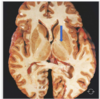

Which of the following structures looks atrophied Thalamus Brainstem Amygdala Hippocampal formation Pituitary

Which of the following structures looks atrophied Thalamus Brainstem Amygdala **Hippocampal formation** Pituitary